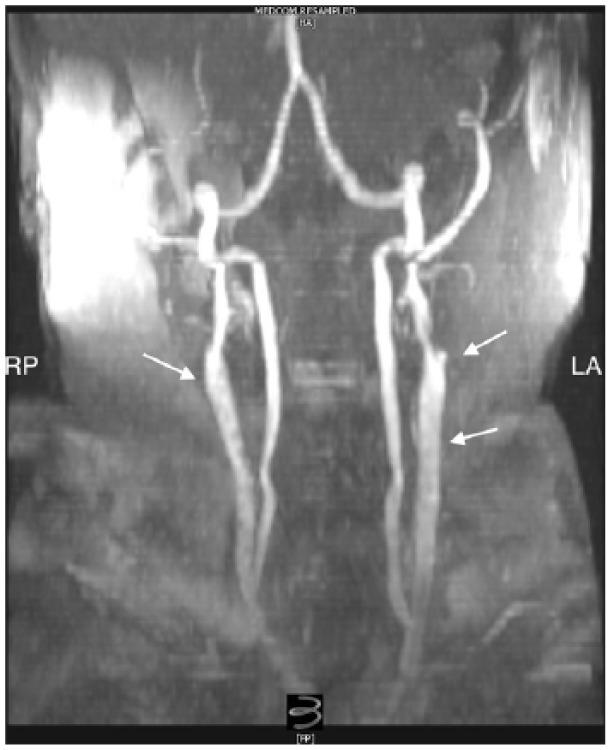

Carotid stump syndrome is defined as the persistence of retinal or cerebral ischaemic events with complete occlusion of the ipsilateral internal carotid artery. The aim of this retrospective cases series was to assess the outcomes for patients with carotid stump syndrome managed with surgical intervention. A series of 11 cases of carotid stump syndrome in nine patients presented to our tertiary vascular centre from October 2004 to February 2016. Indications for intervention were amaurosis fugax, transient ischaemic attacks and stroke. In total, 11 procedures were performed on nine patients including carotid angioplasty and stenting or carotid endarterectomy with patching. The mean follow-up period was 56.6 months. One patient suffered a myocardial infarction 30 days, post-operatively, and one patient was lost to follow-up. In the remaining seven patients, there was a complete resolution of symptoms. There were no incidents of death, stroke, cranial nerve injury, wound haematoma or procedural bleeding. Surgical exclusion of carotid stumps combined with dual antiplatelet agents was found to be a safe and effective treatment method for carotid stump syndrome.

颈动脉残端综合征的定义为同侧颈内动脉完全闭塞时视网膜或脑部缺血事件持续存在。本回顾性病例系列的目的是评估接受手术干预治疗的颈动脉残端综合征患者的治疗效果。2004年10月至2016年2月期间,9例患者中的11例颈动脉残端综合征病例被送至我们的三级血管中心。干预指征为一过性黑矇、短暂性脑缺血发作和中风。总共对9例患者进行了11次手术,包括颈动脉血管成形术和支架置入术或颈动脉内膜切除术加修补术。平均随访期为56.6个月。1例患者术后30天发生心肌梗死,1例患者失访。其余7例患者症状完全缓解。未发生死亡、中风、颅神经损伤、伤口血肿或手术出血事件。发现手术切除颈动脉残端联合双联抗血小板药物是治疗颈动脉残端综合征的一种安全有效的方法。